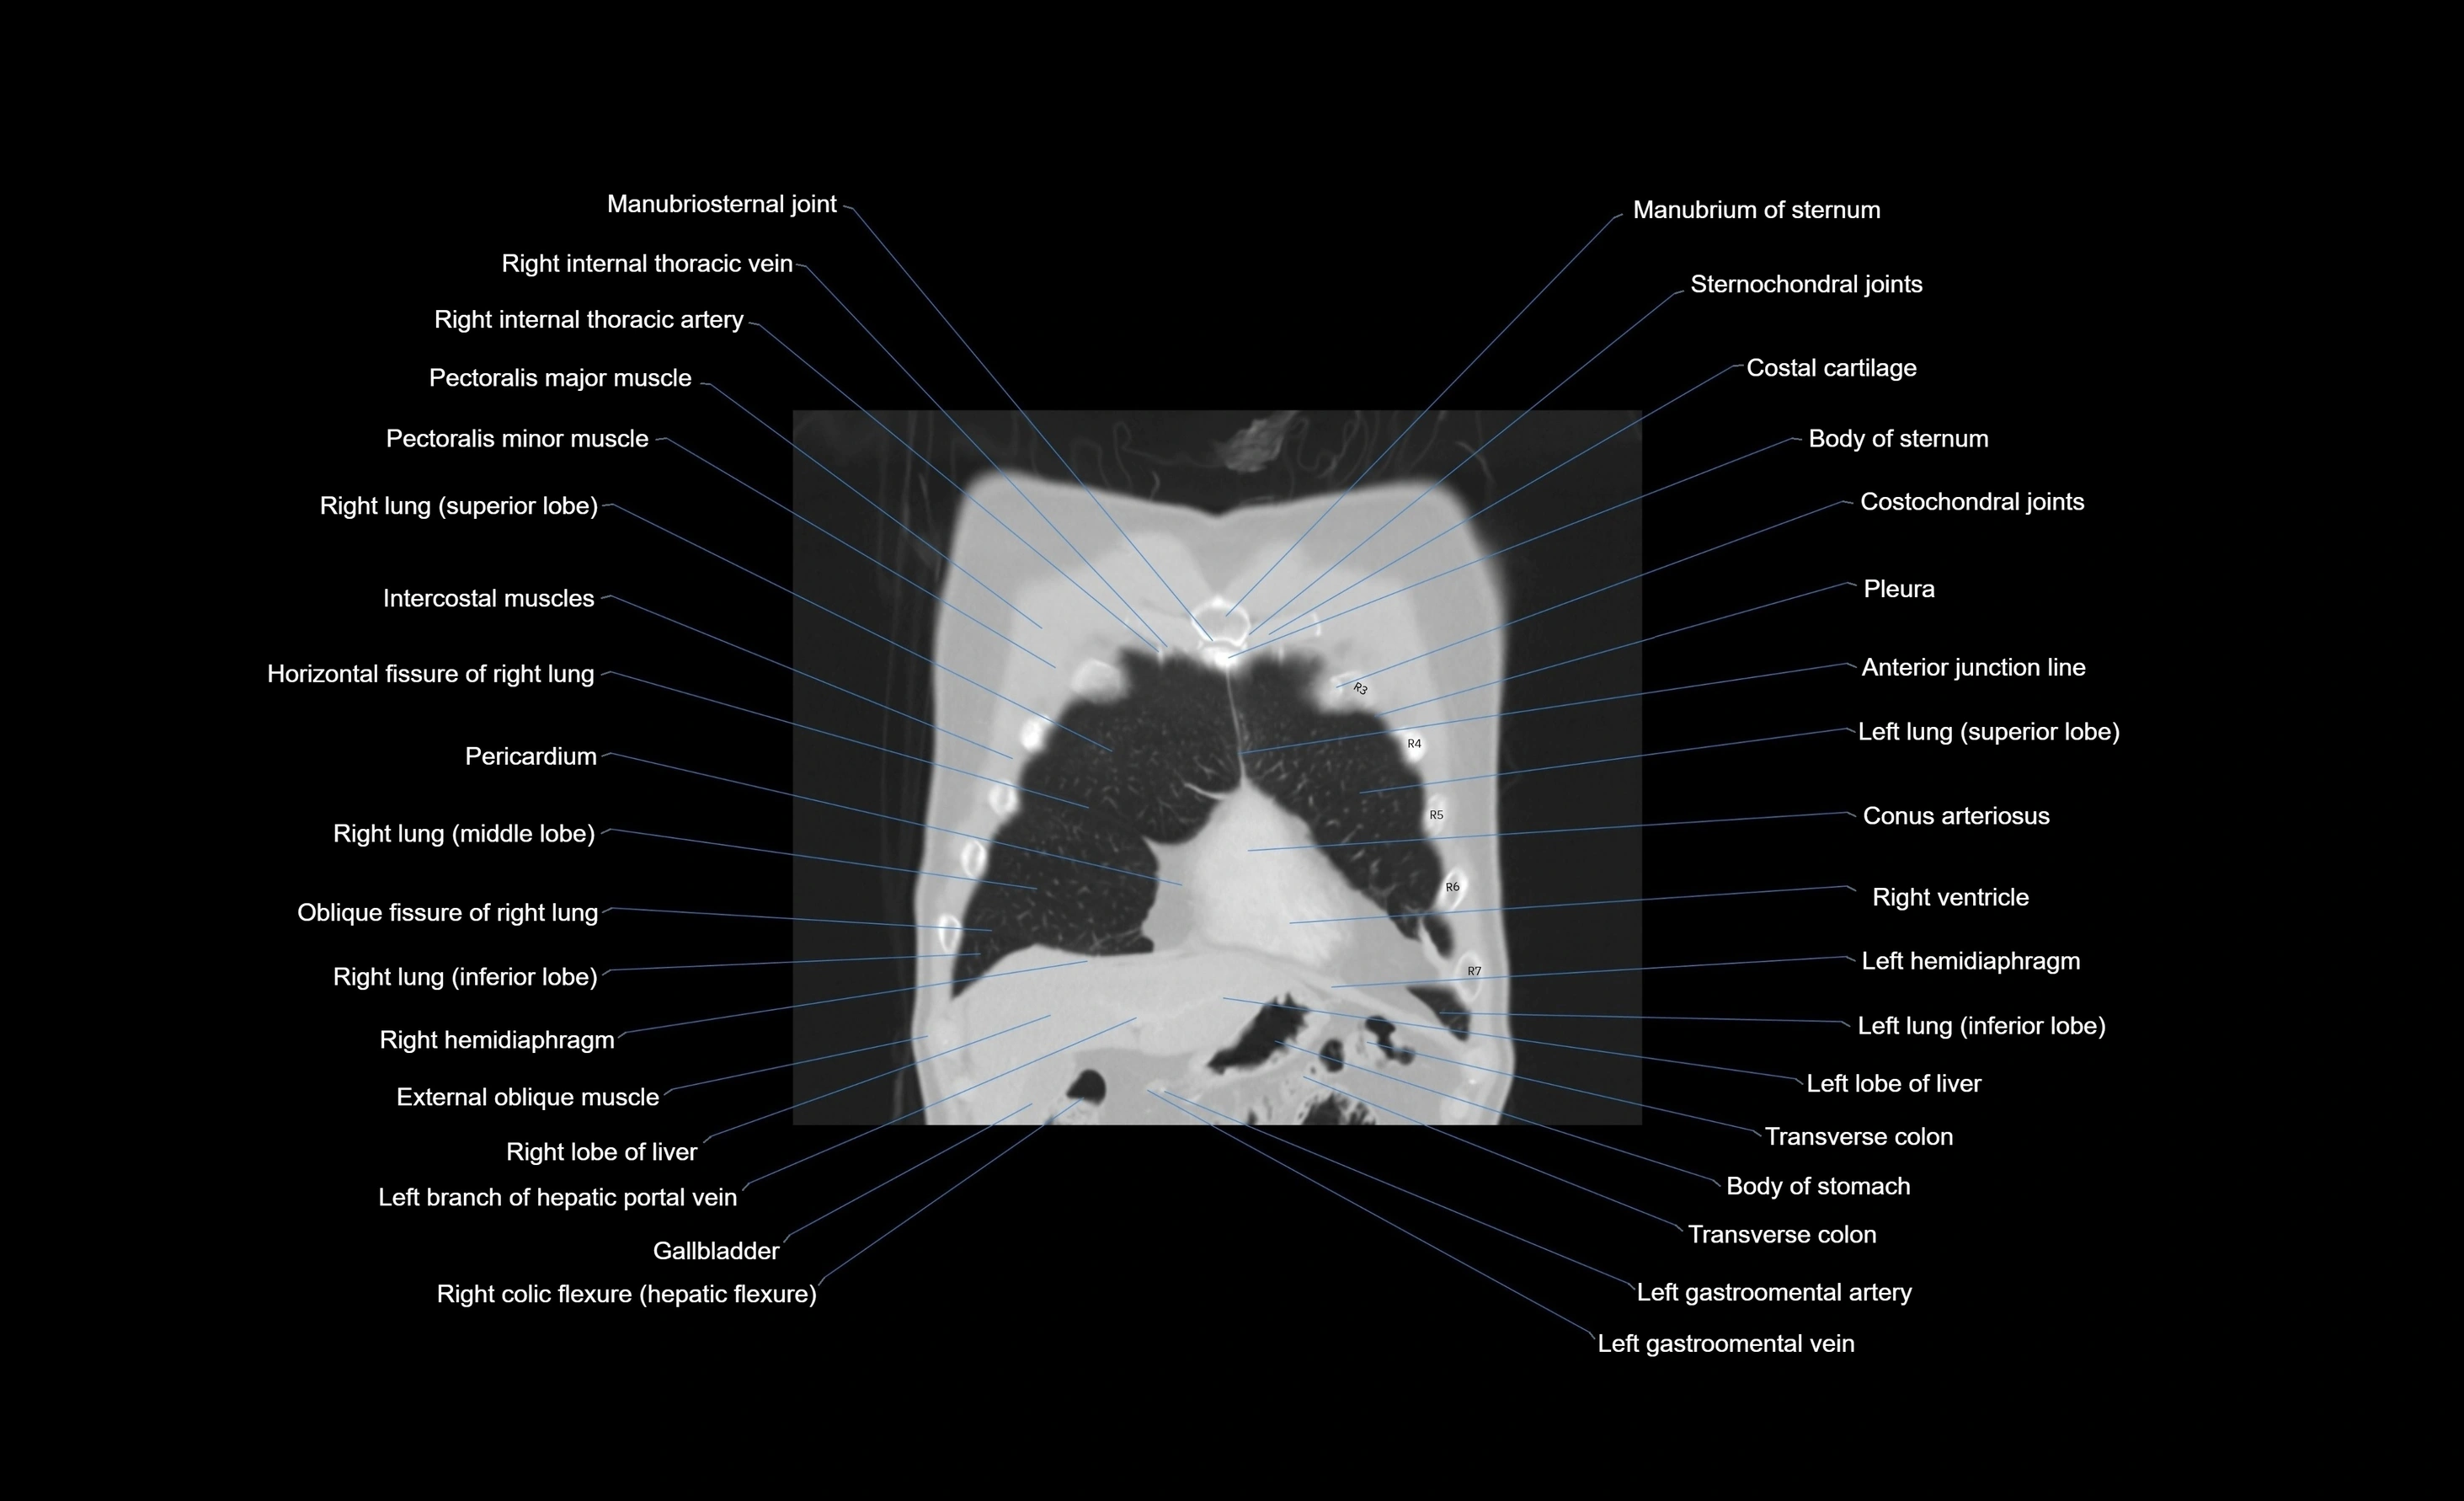

- Body of sternum

- Conus arteriosus

- Costal cartilages

- Costochondral joints

- Horizontal fissure of right lung

- Internal thoracic artery

- Internal thoracic veins

- Left hemidiaphragm

- Left lobe of liver

- Left lung (inferior lobe)

- Manubriosternal joint

- Manubrium of sternum

- Oblique fissure of left lung

- Oblique fissure of right lung

- Pectoralis major muscle

- Pectoralis minor muscle

- Pericardium

- Pleura

- Rectus abdominis muscle

- Right atrium

- Right hemidiaphragm

- Right lobe of liver

- Right ventricle

- Transverse colon